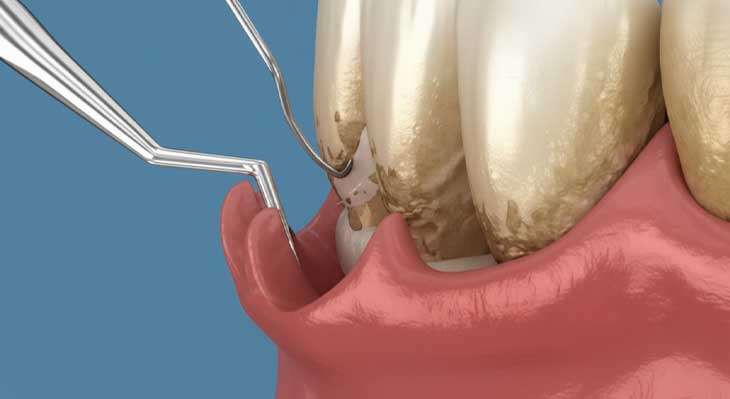

جرم گیری عمقی (روت پلنینگ): این یک روش درمانی برای بیماری لثه (پریودنتیت) است. در این روش، جرم ها و باکتری های نفوذ کرده به زیر خط لثه و داخل پاکت های پریودنتال (فاصله ایجاد شده بین لثه و دندان) پاکسازی می شوند. این فرآیند حتما با بی حسی موضعی انجام می شود و علاوه بر حذف جرم، سطح ریشه دندان نیز صاف و صیقلی می گردد تا بستر مناسبی برای اتصال مجدد لثه به دندان فراهم شود. این درمان معمولا در چند جلسه انجام می شود.

جرم گیری عمقی که به آن تسطیح سطح ریشه نیز گفته می شود، یک درمان تخصصی برای مراحل اولیه و متوسط بیماری پریودنتیت است. این روش به دلیل کار در نواحی حساس زیر لثه، حتما با بی حسی موضعی انجام می شود.

- بی حسی موضعی: دندانپزشک ابتدا ناحیه مورد نظر را به طور کامل بی حس می کند تا بیمار هیچ دردی را احساس نکند.

- اسکیلینگ زیر لثه: با استفاده از ابزارهای اولتراسونیک و دستی، جرم ها و پلاک های تجمع یافته در عمق پاکت های لثه ای به دقت حذف می شوند.

- تسطیح سطح ریشه: در این مرحله، سطح ریشه دندان که به دلیل وجود سموم باکتریایی زبر شده است، صاف و صیقلی می شود. این کار به لثه اجازه می دهد تا مجددا به سطح تمیز ریشه بچسبد.

- تعداد جلسات: این درمان معمولا در دو تا چهار جلسه انجام می شود و تفاوت ژنژیویت لثه و پریودنتیت لثه در نیاز به این نوع درمان مشخص می شود.